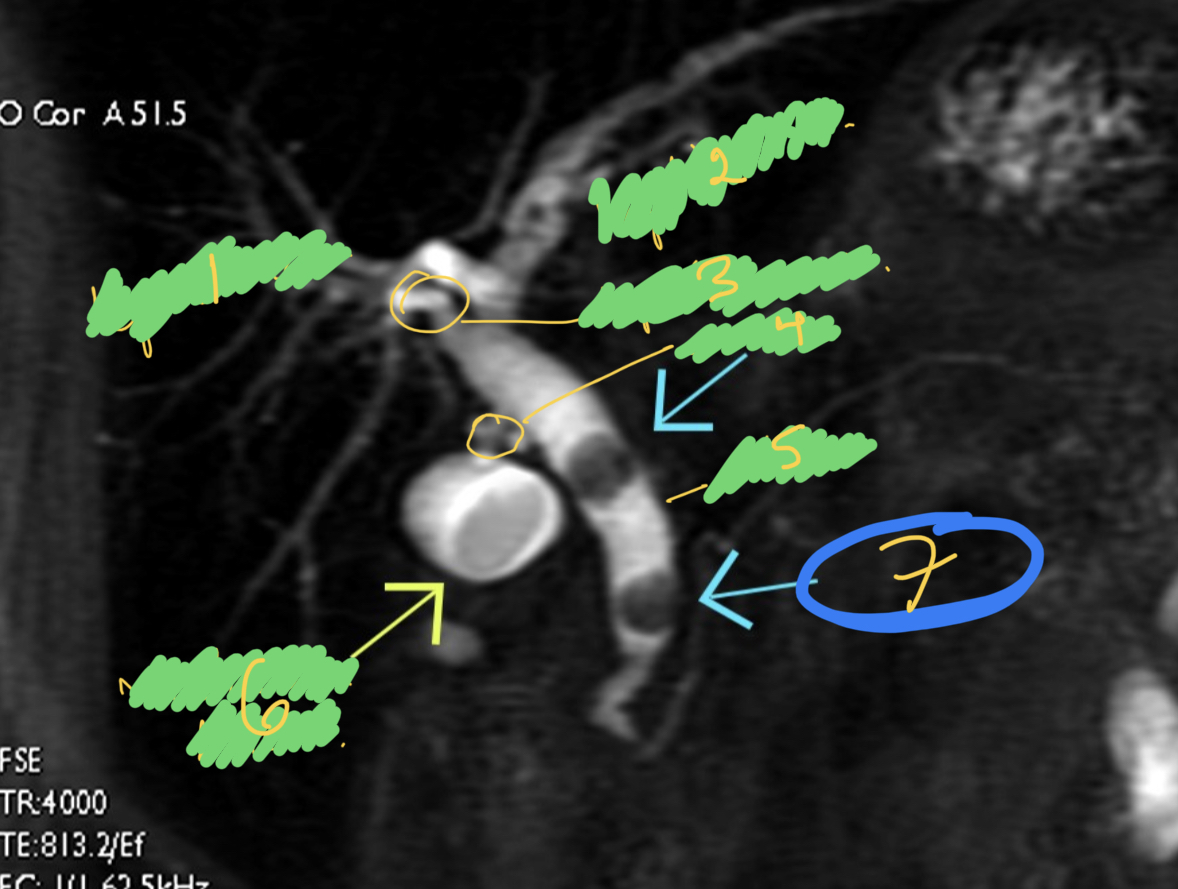

¿Qué observamos en la imagen?

A

1.- Hepática derecha

2.- hepática izquierda

3.- hepática común

4.- arteria cistica

5.- colédoco

6.- vesícula biliar

7.- Litos